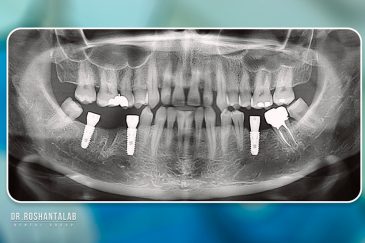

🔸کاشت ایمپلنت فلپ لس یا بدون جراحی و بدون بخیه زیر سه دقیقه

🔸 کاشت دندان یک روزه ( کشیدن و کاشت همزمان )

🔸 ایمپلنت دیجیتال و ساخت روکش دیجیتال

تجربه کاشت دندان دیجیتال و بدون درد در ۳ دقیقه! استفاده از برترین برندها زیر نظر جراح، با هزینه مناسب و خدمات کامل از کاشت دندان تا روکشارتودنسی دندان